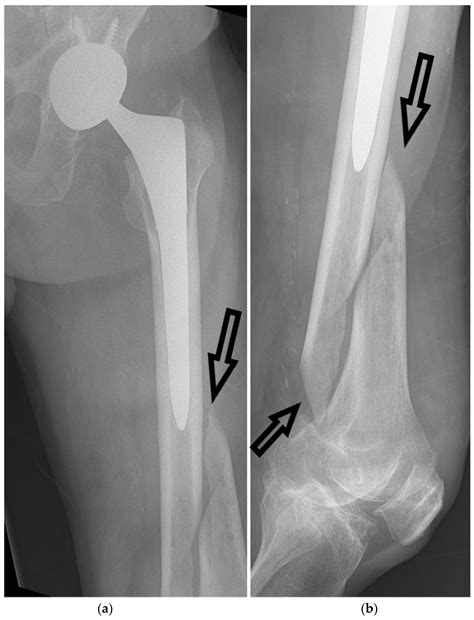

Surgical Treatment

• Open Reduction and Internal Fixation (ORIF): A procedure where the bone is surgically realigned and held in place with plates, screws, or rods.

• Non-Union: Failure of the bone to heal properly, resulting in a persistent fracture.

• Malunion: Healing of the bone in a misaligned position, leading to deformity and functional impairment.